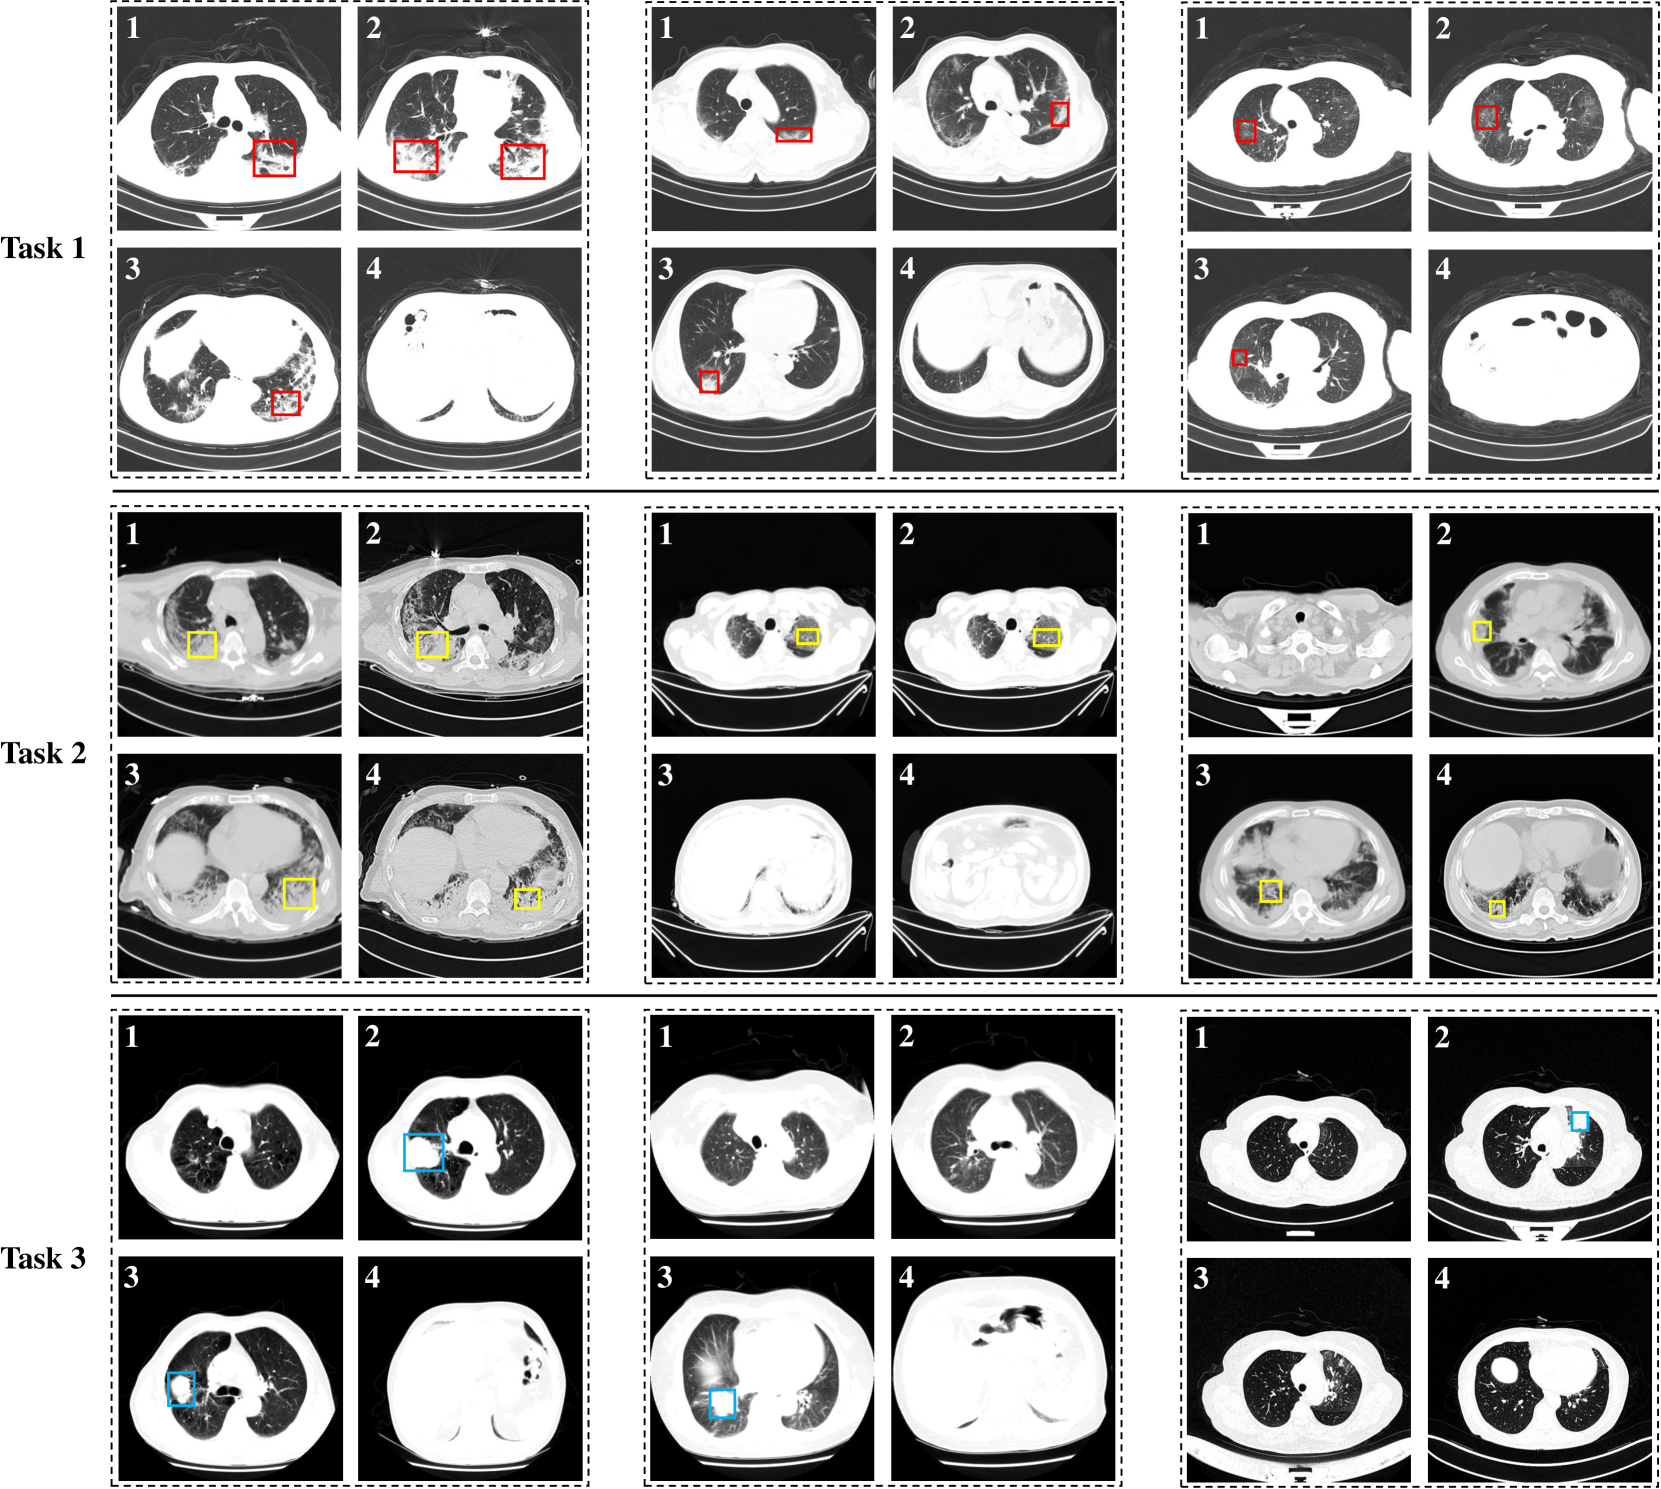

Figure 4: Visualization of CT slices selected by our proposed CSS. The red, yellow and blue boxes mark the lesion areas of NCP, CP and AC, respectively.

We visualize the slices selected by our proposed CSS method, as shown in Fig. 4. In Fig. 4, rows 1, 2, and 3 show the selected CT slices in Task 1, 2 and 3, respectively. Each task displays three cases, with each case retaining four slices. From Fig. 4, we have several observations: (1) the slices selected by our proposed CSS contain lesion areas, indicating that the CSS method can select representative slices to aid in diagnosis; (2) In Task 1 and Task 2, the number of slices with lesions is significantly greater than that in Task 3. For example, in Task 3, only one slice in the second and third cases has AC. This shows that in the entire CT volume, the number of slices indicating AC may be less than those indicating pneumonia. In other words, AC is less obvious on CT and more difficult to diagnose, which is consistent with the experimental results in Section 4.3.